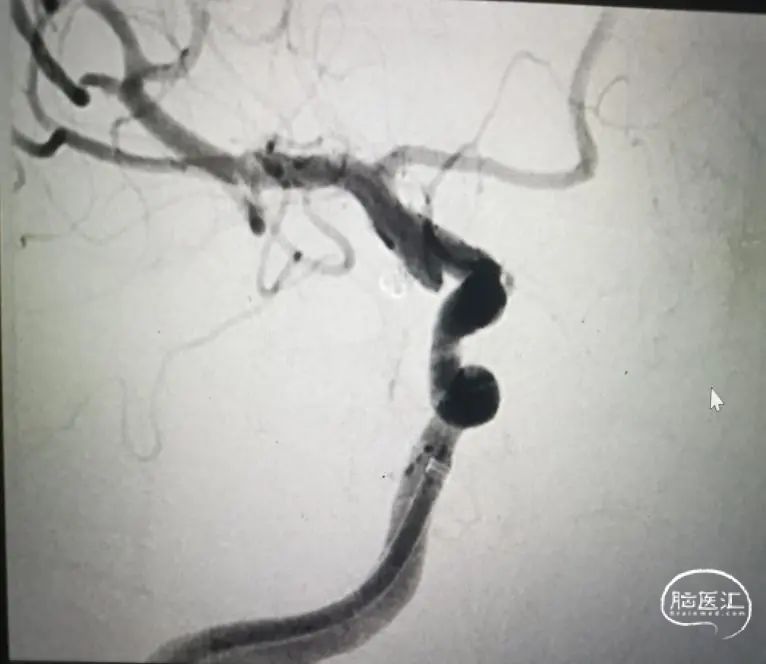

栓塞结束后造影

穿刺右股动脉,造影证实右侧后交通动脉瘤,微小宽颈动脉瘤,5F多功能造影管带通桥银蛇6F-115直奔主题,进入右侧颈内动脉,路径图指引下微导管引导支架微导管到达预定位置,然后通过微导丝引导栓塞导管进入瘤腔,分别依次填入3D2*4cm、1.5*2cm、1*1cm三枚弹簧圈,栓塞结束后造影显示动脉瘤致密栓塞,依次撤出器械,结束手术。

1.微小宽颈动脉瘤开颅风险较高,介入风险亦高。

4.本病例有预置支架微导管的备案,但尽量采用单纯填塞弹簧圈完成了致密栓塞,减少并发症风险。